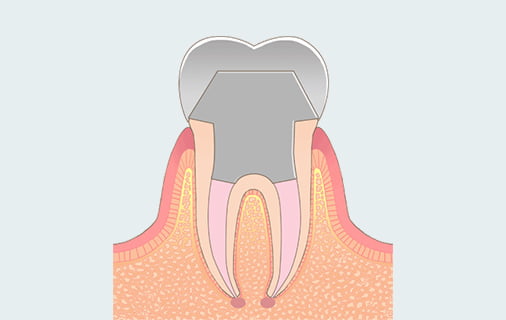

根管充填

無菌状態を維持するために薬剤で根管を密閉します。

歯を補強するための

土台ラスファイバー製の芯棒を入れて歯を補強し割れにくくします。

被せ物の装着

歯の機能を回復させるためのクラウンを装着します。